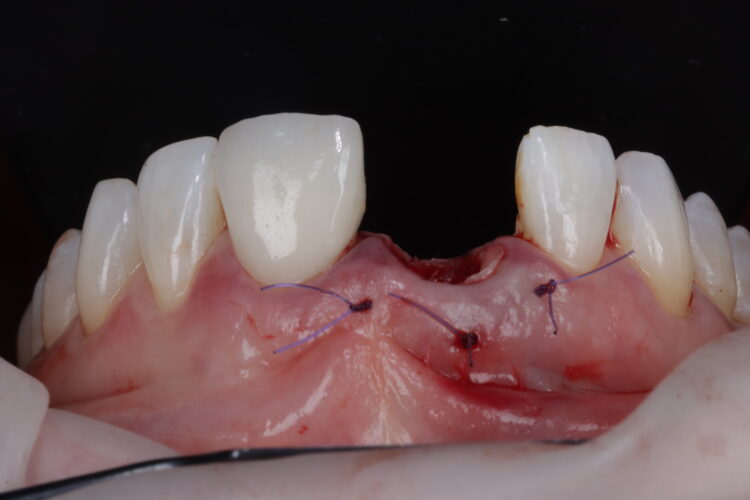

A free gingival graft was harvested from the palate, allowing enough tissue to reach between the base of each papilla and this was de-epithelialised to obtain the connective tissue. A thickness of 1mm is adequate, but in this instance, it was made intentionally thicker at the disto-buccal aspect to help plump up the papilla where bone loss was greater. The connective graft tissue was stabilised with three resorbable sutures placed, positioning the connective tissue graft 1mm below the free gingival margin.

A bone graft was then performed, adding MinerOss® Blend (BioHorizons Camlog) to the jump gap. This affords an ideal combination of cortical and cancellous bone, delivering high bone density and reliable revascularisation to ensure the fast and predictable turnover of bone.

The temporary restoration was then reintroduced and the surgical site closed tension-free. Vertical sling sutures were placed through both papillary areas over the contact points to hold the tissue up, create a prosthetic sealand to combat natural shrinkage.

A post-operative radiograph was taken to confirm that the crestal bone was not compressed and there was no convexity in the area to allow space for the soft tissue graft to expand, proliferate and grow.